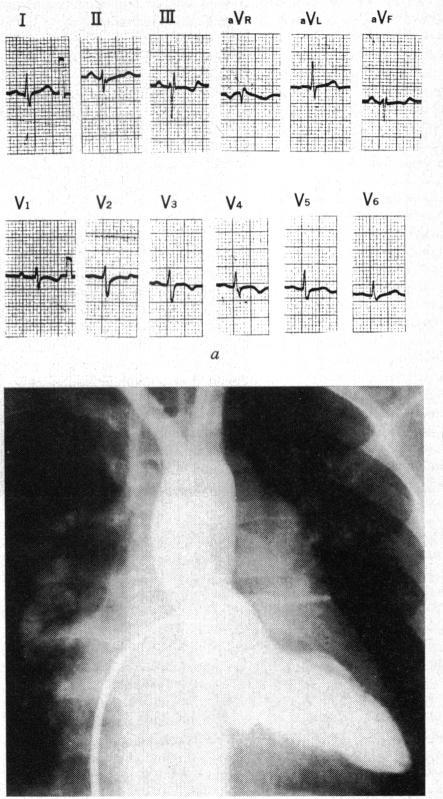

Electrocardiogram of secumdum type atrial septal defect simulating endocardial cushion defect.

Three groups of patients are identified in the series of secumdum atrial septal defect with left axis deviation in an analysis of 910 patients of secundum atrial septal defect with or without other accompanying anomalies: 1) 12 patients with isolated ostium secumdum defect; 2) 5 patients with associated prolapse of posterior leaflet of the mitral valve; 3) 4 patients with associated hypertrophic cardiomyopathy and/or single (left) coronary artery. The findings of these 21 patients with proved secumdum atrial septal defect are analysed. The combination of such anomalies should be considered in the differential diagnosis of primum endocardial cushion defect from the electrocardiographic viewpoints.

在对910例继发孔型房间隔缺损患者(无论有无其他伴随异常)进行分析时,发现了三组伴有左轴偏移的继发孔型房间隔缺损患者:1)12例孤立性继发孔缺损患者;2)5例伴有二尖瓣后叶脱垂患者;3)4例伴有肥厚型心肌病和/或单支(左)冠状动脉患者。对这21例经证实的继发孔型房间隔缺损患者的检查结果进行了分析。从心电图角度来看,在原发孔型心内膜垫缺损的鉴别诊断中应考虑这些异常的组合。